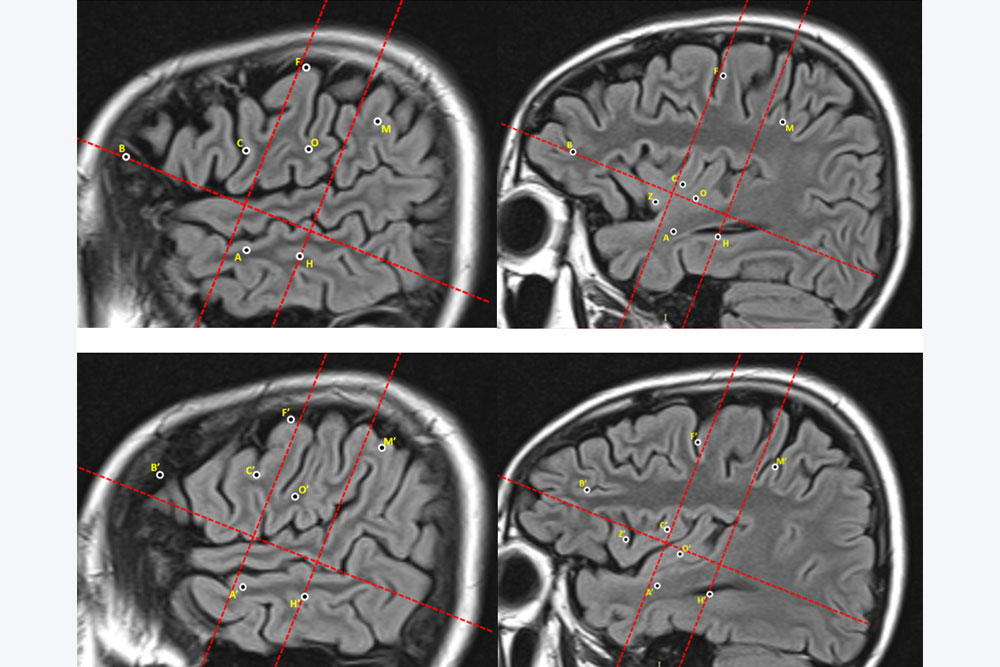

继发性癫痫是神经外科常见病,该种疾病通常发生在免疫力低下的儿童以及老年人身上。要想确诊是不是继发性癫痫,需要进行脑脊液检查、神经电生理检查、头颅核磁共振检查、头颅CT检查、血常规检查,此病经检查确诊后,要及时用药治疗,最常用的药物是苯妥英钠、卡马西平和丙戊酸钠。那继发性癫痫的严重危害都有哪些呢?下面详细介绍。